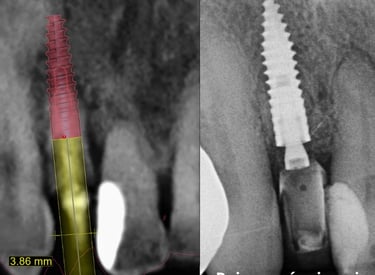

Curso especializado em técnicas de reabilitação com implantes dentários utilizando técnicas atualizadas e avançadas com planejamento digital em softwares específicos.